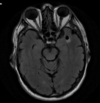

A

Cisto epidermóide

Hipersinal na difusão

Sinal heterogêneo no FLAIR

Extra-axial

Cisto epidermóide do SNC

Sinal heterogêneo no FLAIR e Hipersinal na DWI

Extra-axial nas sisternas da base.

Formações serpiginosas, enoveladas com flow void (preto) em T1 e T2 dando aspecto de saco de vermes negros. Há enchimento pelo contraste; Maioria supratentoriais. Áreas de isquemia adjacente - atrofia do parênquima (roubo de fluxo pela MAV).

Cisto epidermóide do SNC Sinal heterogêneo no FLAIR e Hipersinal na DWI Extra-axial no angulo pontocerebelar